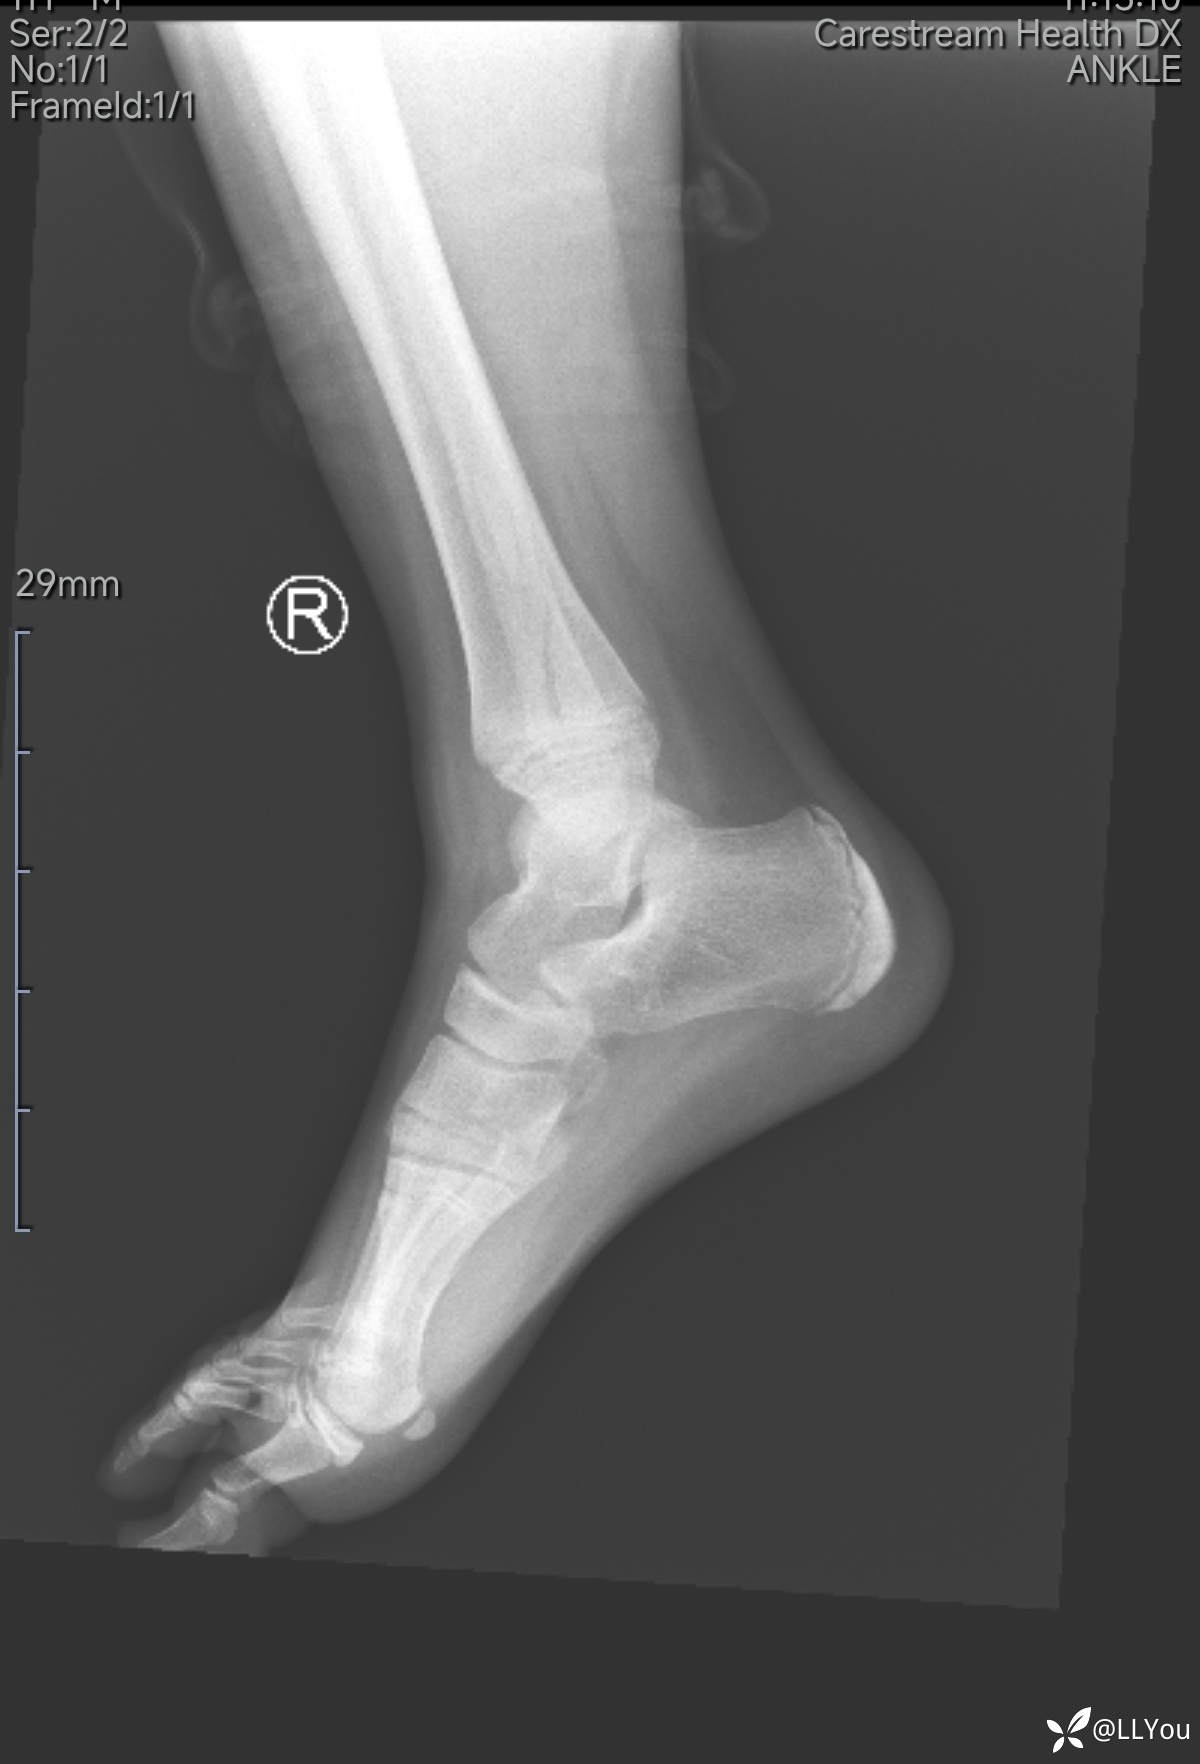

病人,男,11岁

踝关节外伤后肿痛2小时来诊

查体:踝关节轻度肿、压痛,活动稍受限。

踝关节X光片,见下图。

儿童踝关节损伤有独特之处

诊断需谨慎!